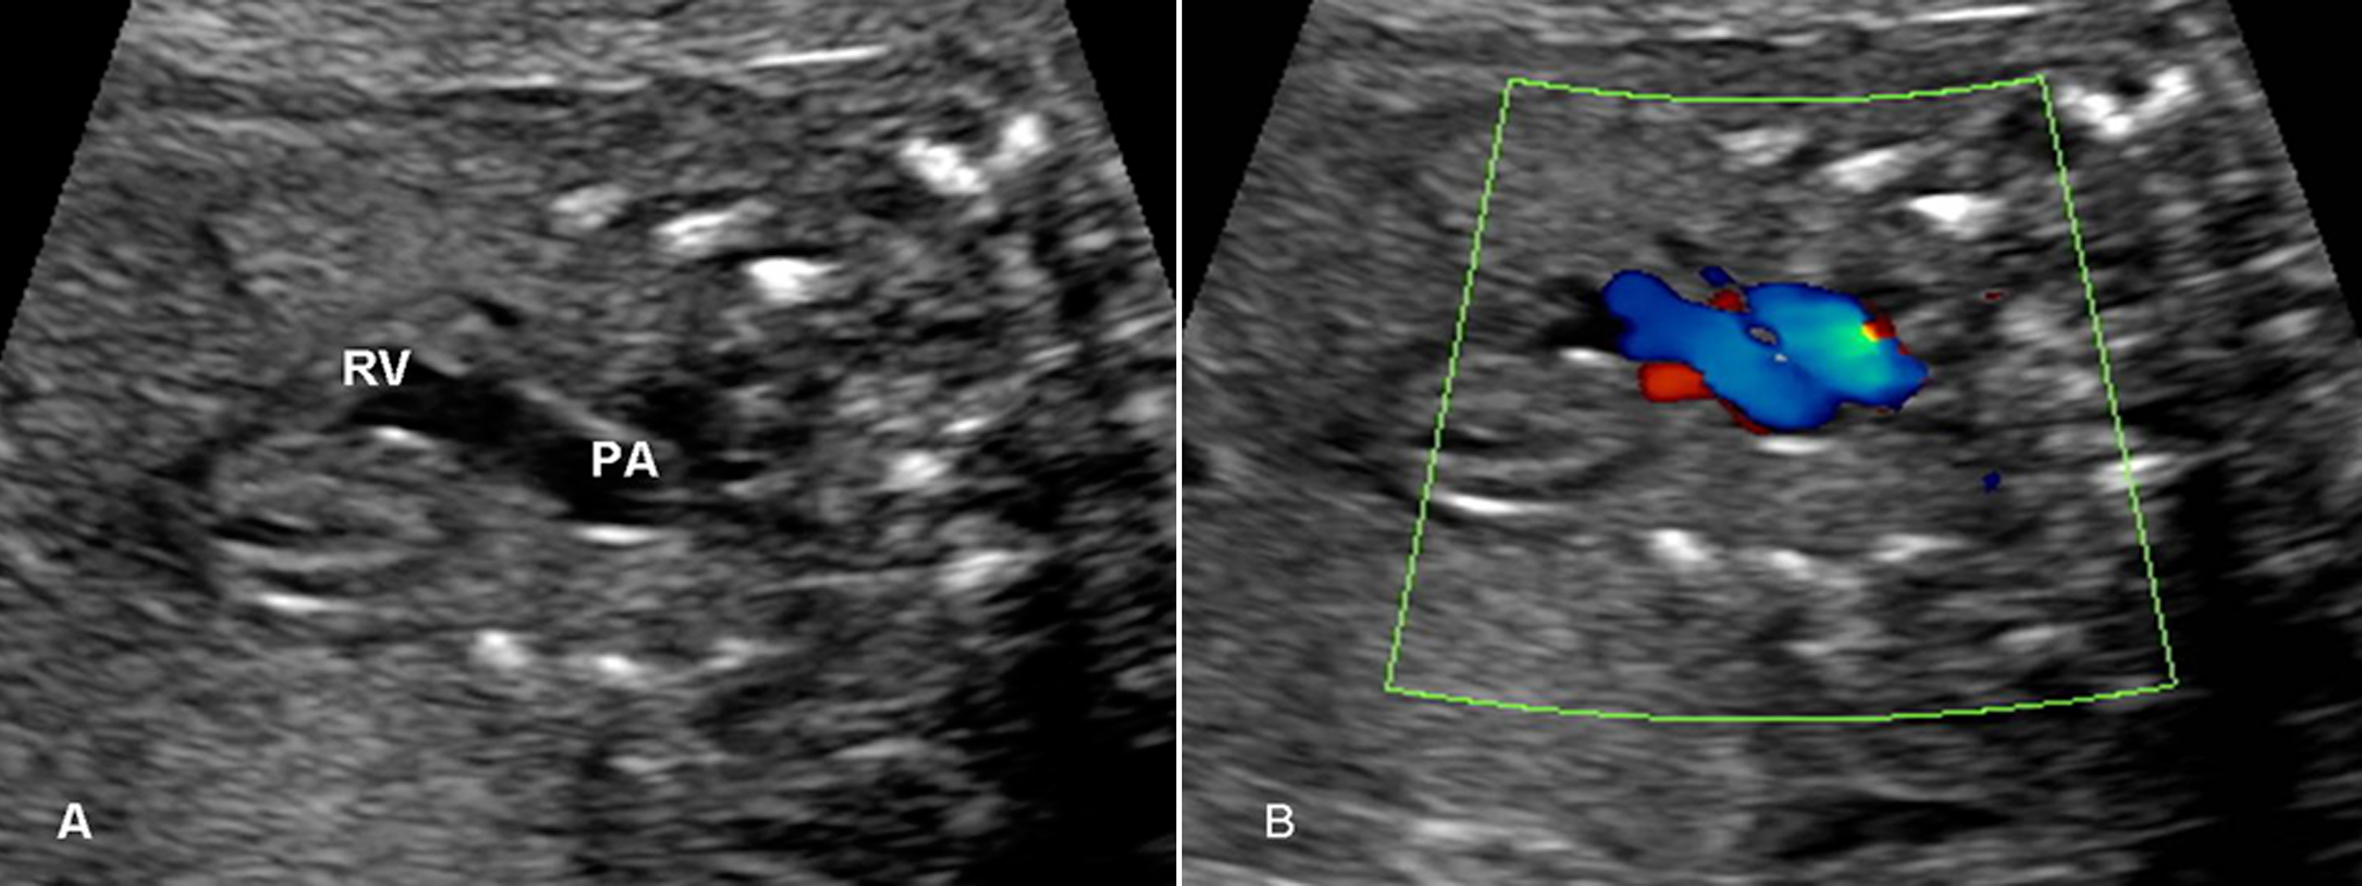

2.肺动脉瓣及PA 显示相对困难,有报道认为胎儿PA的血流显示率不足一半,并且血流速度最快的部位在动脉导管处。PA的频谱显示为非对称性的三角形,上升速度大于下降速度(图3、图4)。

图4 右室流出道切面观(A)及血流(B)